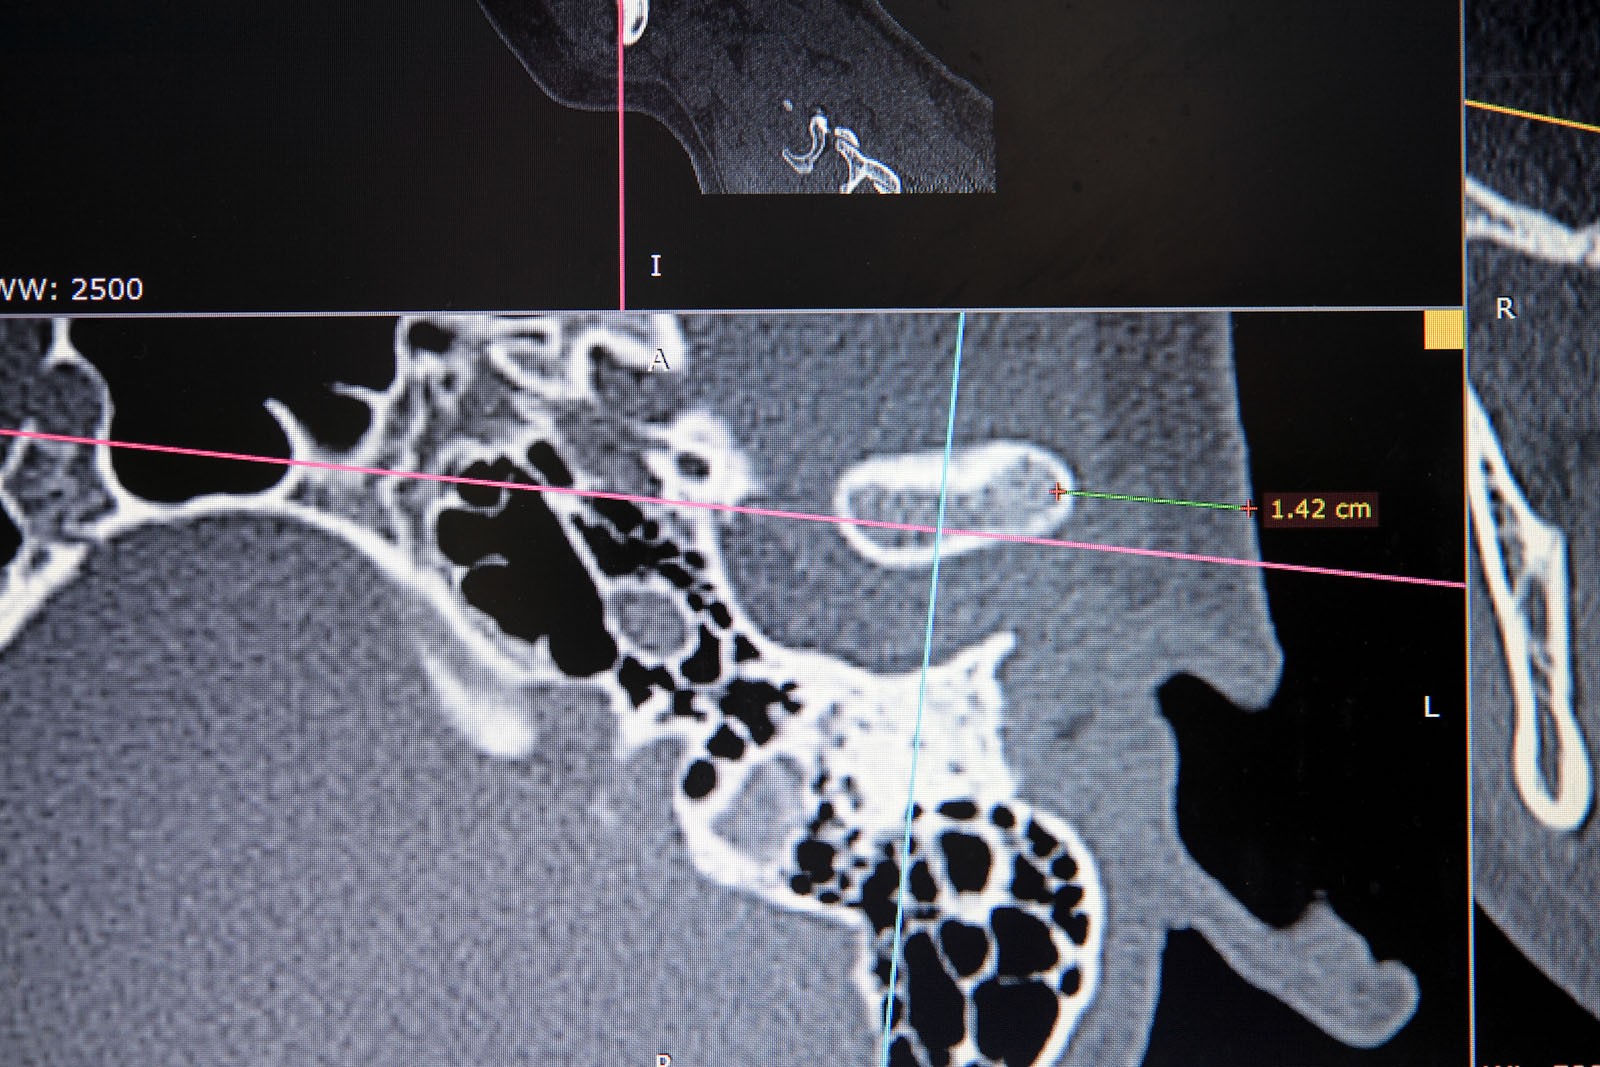

Metoda Gerbera jako punkt wyjścia dla analizy traktuje staw skroniowo-żuchwowy. W relacji do jego funkcji bierze pod uwagę pozostałe ogniwa układu stomatognatycznego. Staw skroniowo-żuchwowy jest działającym synchronicznie symetrycznym elementem anatomii twarzoczaszki, który pozwala na otwieranie ust i funkcje z tym związane. To staw o złożonej budowie, w jego skład wchodzą: dołek stawowy kości skroniowej, który stanowi panewkę stawową, wyrostek kłykciowy, krążek stawowy i torebka stawowa. Krążek zbudowany jest z chrząstki i dzieli jamę stawową na dwie części: górną i dolną. Podczas ruchów opuszczania żuchwy (otwierania ust) krążek stawowy przesuwa się do przodu i dołu. Wraz z krążkiem przesuwa się wyrostek kłykciowy głowy żuchwy po obu stronach. W ruchu przywodzenia żuchwy (zamykania ust) krążek stawowy i wyrostek kłykciowy żuchwy wracają na swoje miejsce do pozycji wyjściowej. Stawy są sprzężone ze sobą czynnościowo (ruch następuje równocześnie w obu stawach) i anatomicznie (łączy je trzon kości żuchwy), stąd też nieprawidłowe asymetryczne obciążenia stawów są najczęstszą z przyczyn zaburzeń narządu żucia.

W ocenie wewnątrzstawowych patologii pomocna jest diagnostyka obrazowa. Konwencjonalne zdjęcia radiologiczne OPG, tomografia komputerowa oraz stożkowa tomografia komputerowa CBCT pozwalają na ocenę elementów kostnych stawu skroniowo-żuchwowego. Ocenę tkanek miękkich zlokalizowanych wewnątrzstawowo umożliwia rezonans magnetyczny NMR.

W pierwszym etapie wykonuje się modele robocze, które są montowane w opracowanym przez prof. Gerbera artykulatorze. Tak zwany condylator pozwala na symulację trójwymiarowych ruchów głów żuchwy. Pozwala na zweryfikowanie poprawności relacji pomiędzy łukiem zębowym górnym a dolnym. Po dokładnym zbadaniu funkcji i morfologii stawu sż, wykonaniu pomiarów oraz ocenie stanu zdrowia zębów zostaje opracowany indywidualny plan leczenia zgodny z uwarunkowaniami pacjenta.